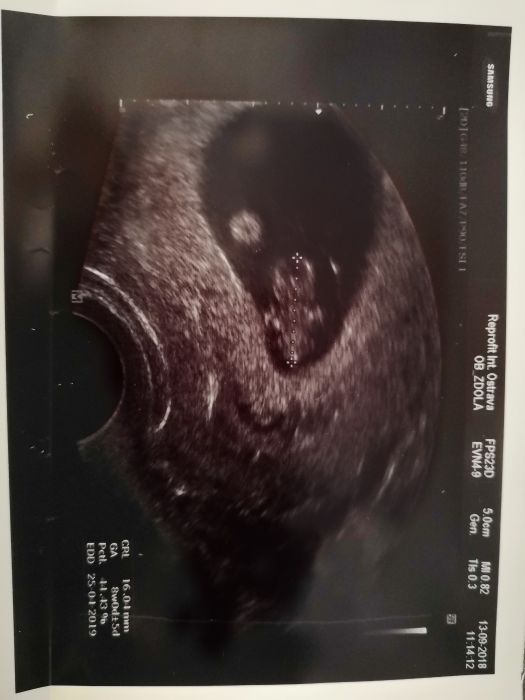

Maminky co je prosím ta kulička vedle kinder vajicka? Je to hematon? Dr. nic neříkal ale pořád přemýšlím co to je?

Hematom to nejni. V kolikátém tt jsi?